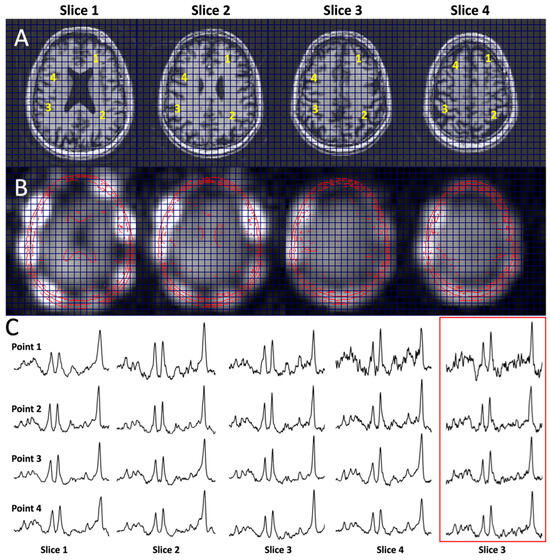

Figure 4 shows the performance of the multi-slice J-refocused RSI. With the simultaneous (rather than cascaded) multi-slice excitation RF pulses, the CSDE shift in the slice direction is 2.2 mm between NAA and Cr. The SNR is consistent with the four-fold-longer acquisition time of 8.8 min used for the multi-slice study in comparison with the matched 2.2 min single-slice acquisition (Figure 4C).

Figure 4. Multi-slice Hadamard J-refocused RSI. (A) Scout T1, (B) magnitude NAA images, and (C) sample spectra as indicated from four-slice J-refocused RSI using simultaneous Hadamard slice encoding; 7 mm slice thickness, 2 mm slice gap, ~9 min total duration, and TE 38 ms. Spectra at yellow numbered points (1, 2, 3, 4) in (A) for slice 1–4 are shown in (C); the red-boxed spectra shown in (C) are from the matched single-slice RSI for slice 3 for a 2.2 min duration.